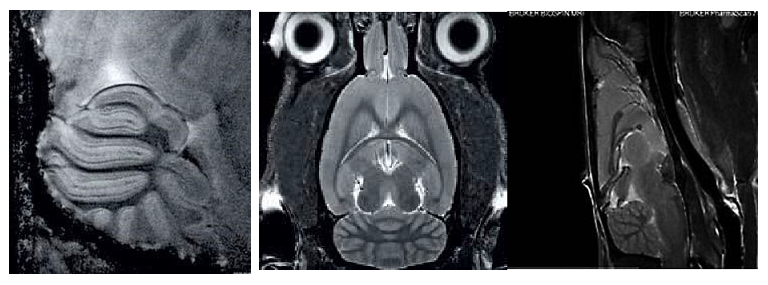

1、高分辨率神经解剖结构

布鲁克结合超高磁场,先进的相阵控线圈和谱仪技术提供完美品质的结构形态成像。超高空间分辨率可以显示精细的显微组织结构。领先的磁共振成像技术在超高磁场下提供完美的对比度。

磁共振成像低温探头增加150%的灵敏度,清晰显示小鼠脑部细胞层状结构(小脑的颗粒层和浦肯雅细胞层),空间分辨率达到 50µm: